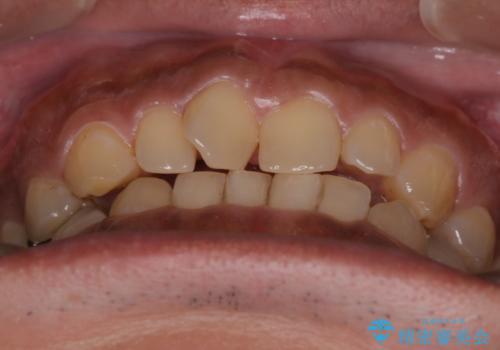

【モニター】インビザライン 前歯の捻れを治したい

- 30代男性

- 治療計画

- 上下の前歯のがたつきを主訴に来院されました。インビザラインで治療可能と判断致しましたので、IPR(歯と歯の間を削る処置)と歯列弓拡大をして

がたつきをとる治療計画を立てました。

マウスピースをしっかり使用していただいたことで、主訴である前歯のがたつきも改善され

リファイメントも1回のみで治療を終了することが出来ました。